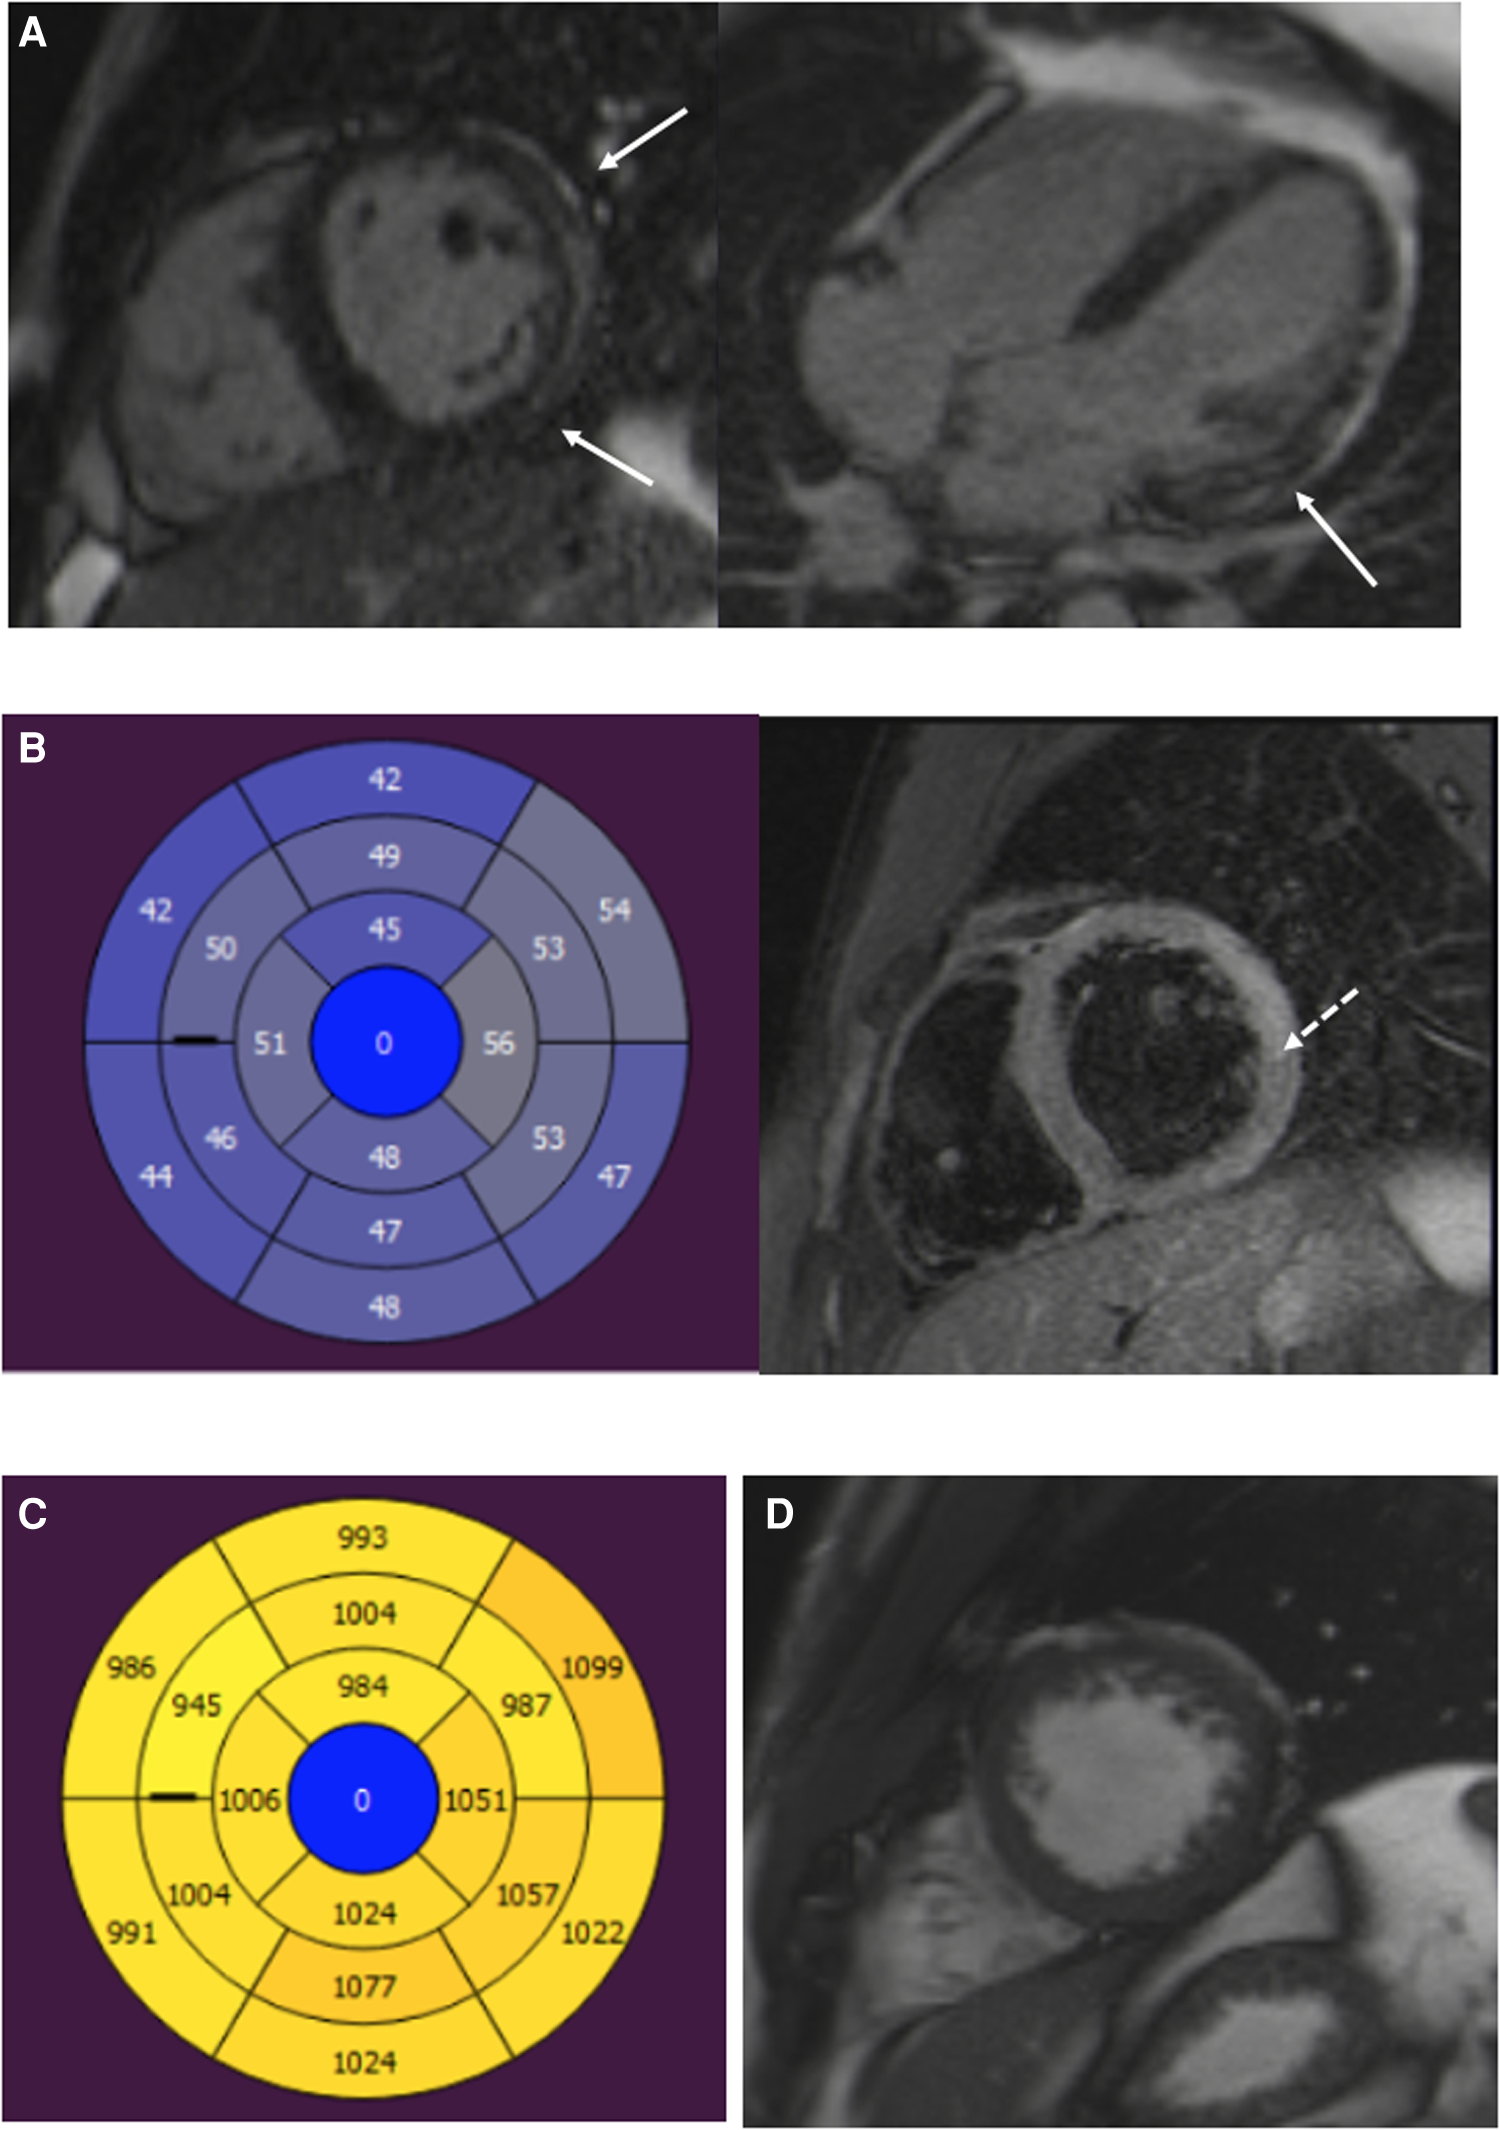

Figure 3

A 22-year-old male patient with myocarditis. (A) Short-axis and four-chamber LGE images show subepicardial enhancement of the lateral wall (arrows). (B) T2 mapping and T2 fs images show myocardial edema in the lateral wall (dotted arrow). (C) T1 relaxation times are elevated in the inferior and lateral segments. (D) Normal trabeculation of the LV apex. LGE, late gadolinium enhancement; LV, left ventricular.